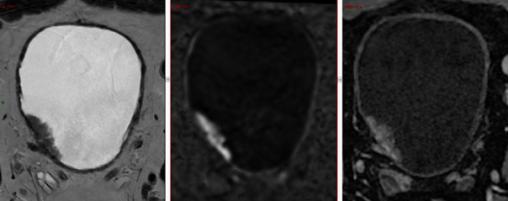

IRM en séquences T2, diffusion et T1 gadolinium : tumeur de vessie de 34 × 10 mm à la face latérale droite, à base d’implantation sessile, au contact du méat urétéral, VIRADS 3/5 (pas de modification du signal de la couche musculaire). Absence d’adénopathies pelviennes, d’extension extravésicale ou d’atteinte du cadre osseux. À l’examen anatomopathologique : classification Ta de haut grade/G3.